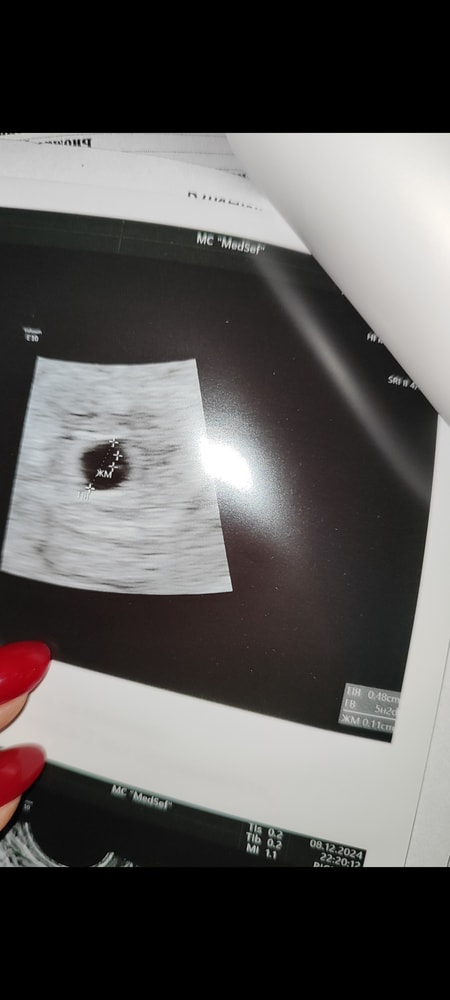

Вот покажу вам почему ждала я, у меня и при 4,8 мм и через неделю при 6,9 мм был желточный мешок. Поэтому мне говорили что есть маленькая надежда, но и то на втором УЗИ мне сказали что её уже нет, эмбрион уже должен быть. Если у вас на 6 мм ничего не было, то я думаю это было оправданное решение и не было необходимости что-то ждать.